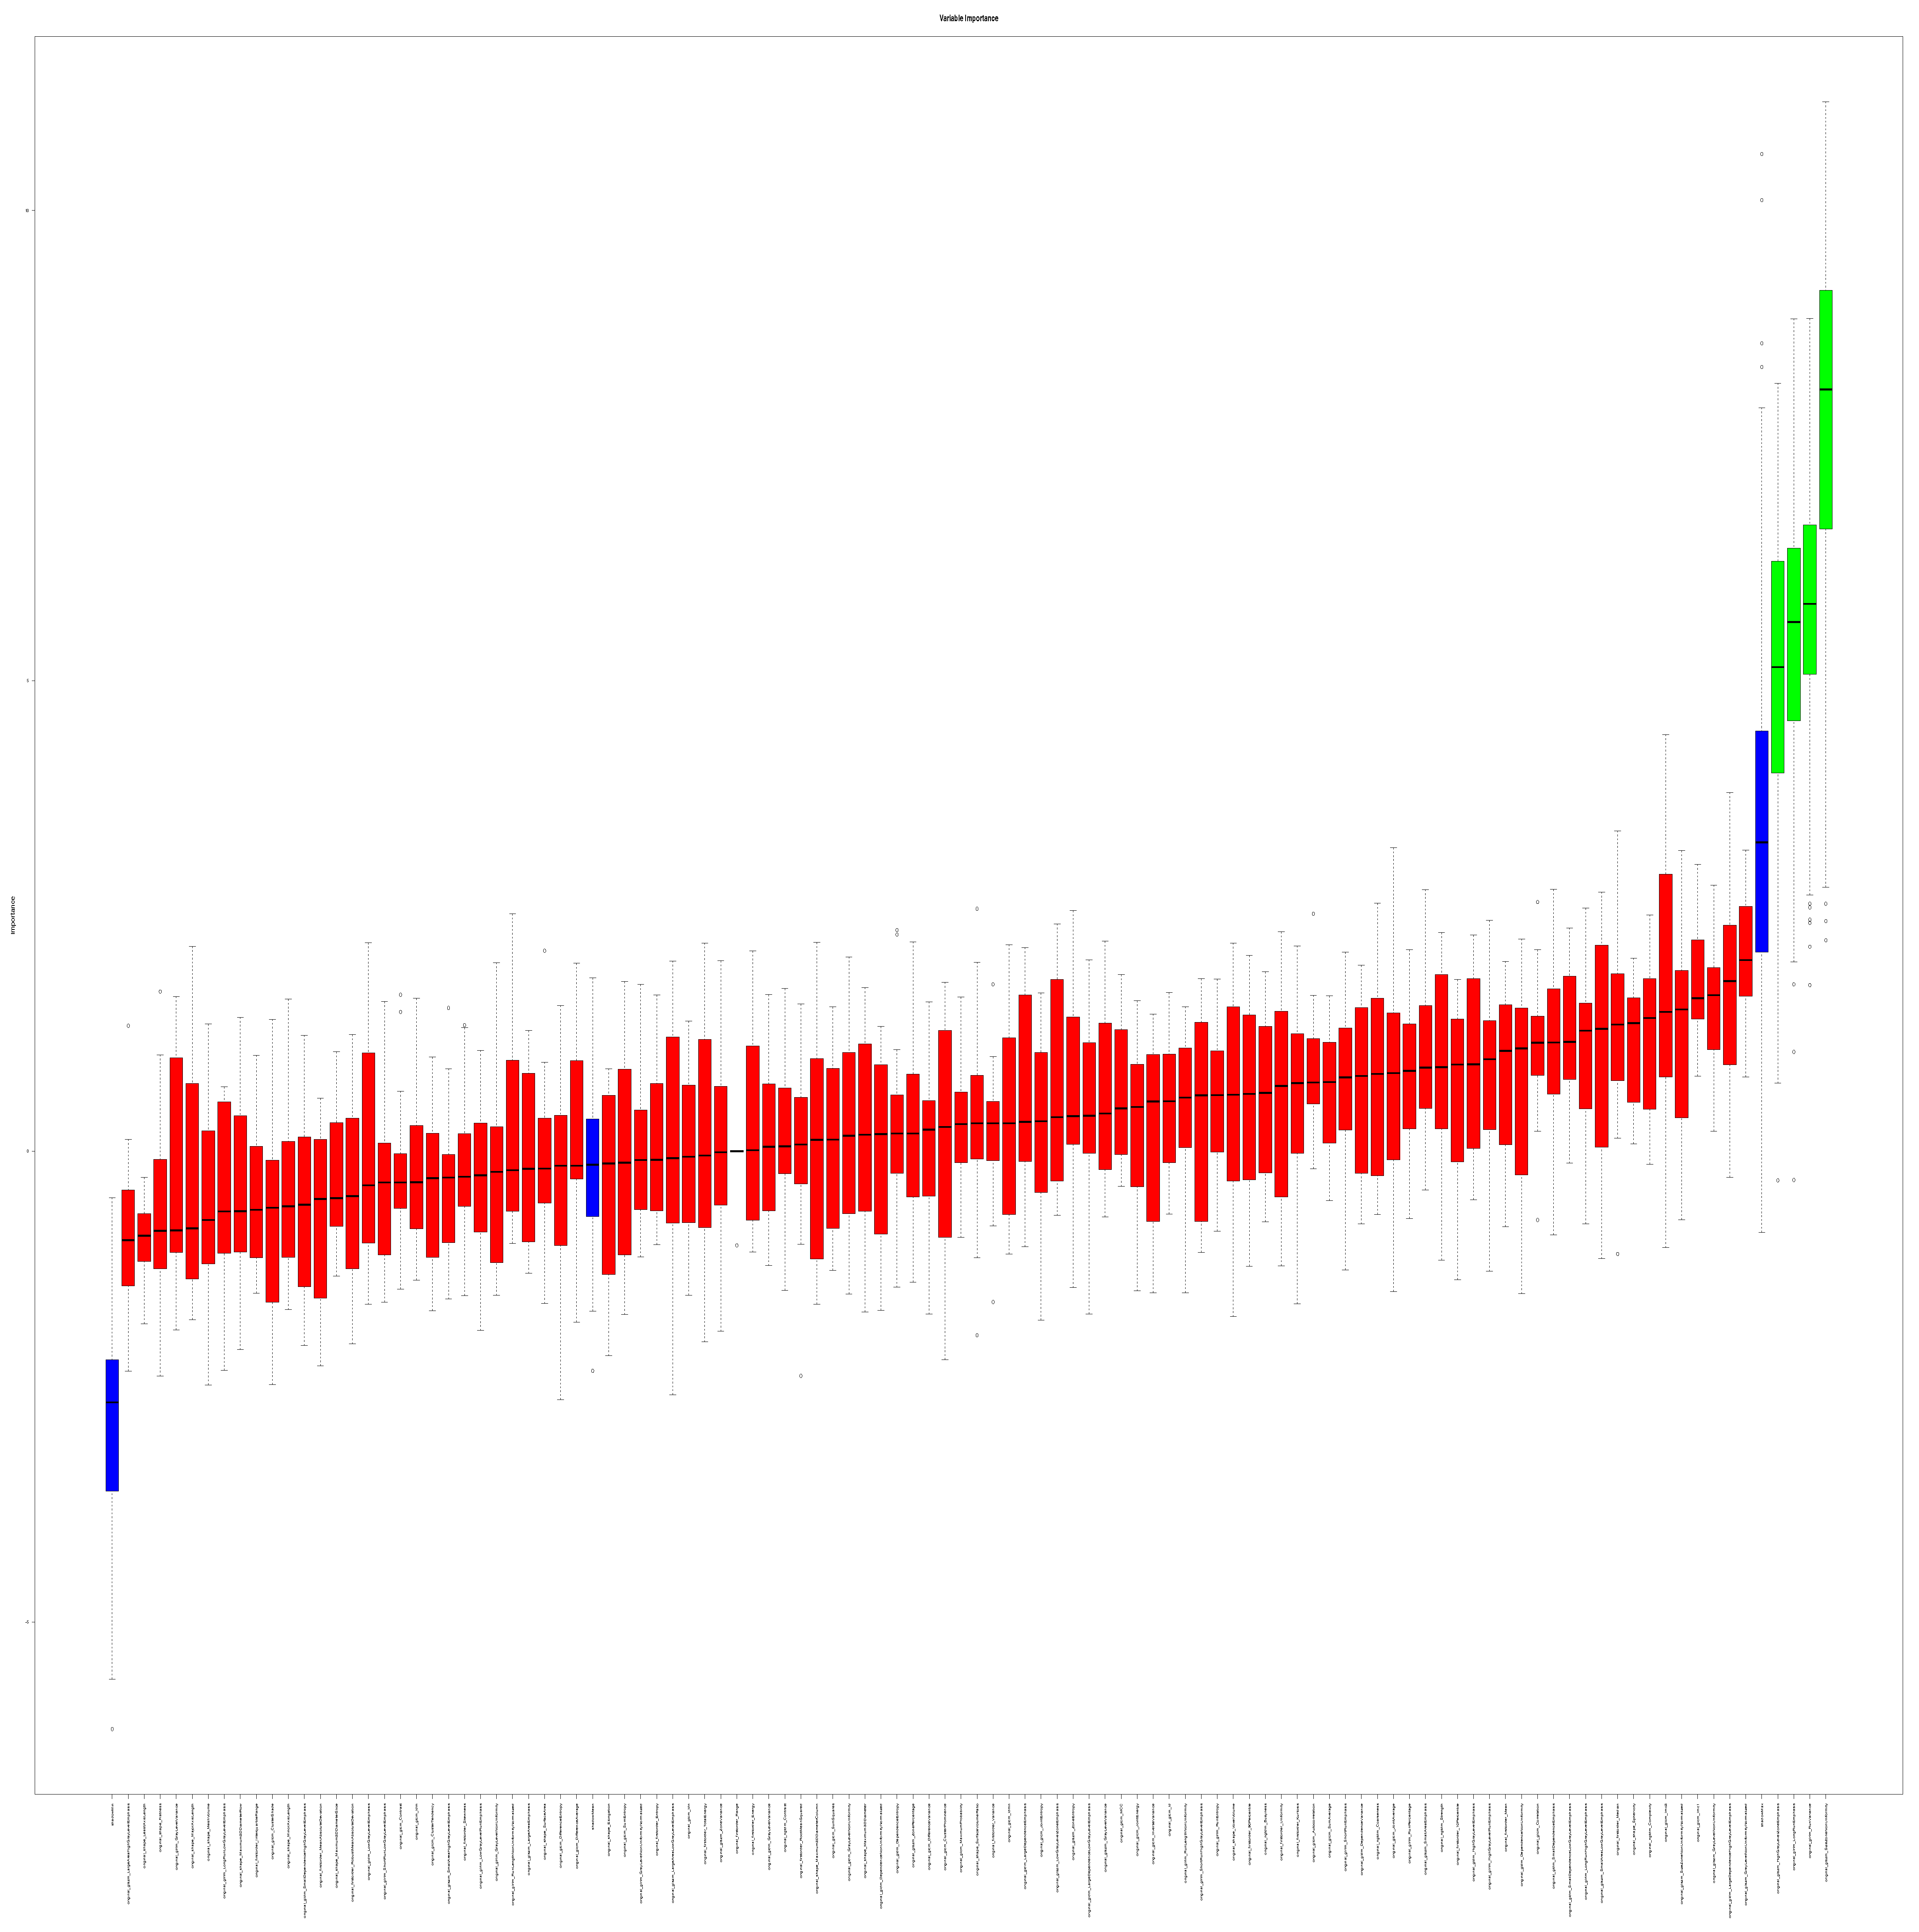

3.3. Feature Selection

3.4. Internal Validation